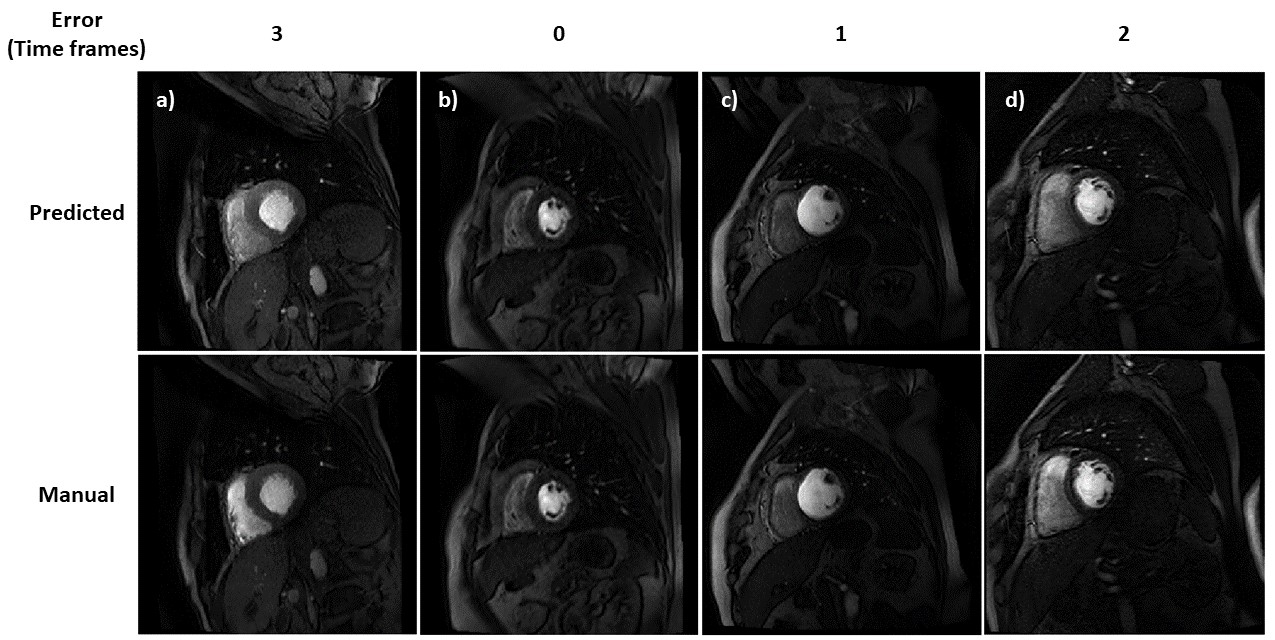

Convolutional neural networks

A network where all units are connected to all units in the previous layer is said to be fully-connected. This design is inefficient or infeasible for image processing because of the high dimensionality of the inputs (the dimensionality is equal to the number of pixels or voxels in the image). An alternative network design, more suitable for image processing, is the convolutional neural network (CNN), as visualised in Figure 5.3. A CNN combines inputs from only a small region of the previous layer (commonly referred to as the receptive field and designed to loosely resemble the visual cortex). This is implemented as a learnable kernel being convolved with the output of the previous layer to generate the input for the current layer. The convolutional kernel is designed to be significantly smaller than the size of the activation it is being convolved with. This enforces sparse interactions between layers and allows the extraction of low level features, such as edges, without considering the whole image. Parameter sharing is also used such that the same kernel is applied to all inputs to a layer. This aids the training process by greatly reducing the number of parameters to be learned. CNNs also encourage translational invariance in the predictions. Since a kernel slides over the whole input it will detect the same features regardless of their position. This is useful, for example in classification tasks, when it only matters if an object is in an image and not where it is Goodfellow2016.

Refer to caption

Fig. 5.3: A convolutional neural network. This shows the layers of the CNN downsampling the input image and producing a 3D volume of activation (left), and a unit connected to a small receptive field in the previous layer (right), image taken from https://cs231n.github.io/

U-Net

The most commonly used network architecture for medical image processing is the U-Net Ronneberger2015. This is a fully-convolutional network in that it only uses convolutional layers, and is illustrated in Figure 5.4. The architecture has an encoder-decoder structure. The encoder downsamples the input image, using max-pooling, to create a low-dimensional embedding. The multi-step downsampling allows the learning of feature representations at different image scales. The decoder, takes the low-dimensional embedding and upsamples it to try predict the desired output, typically a segmentation map. The network also utilises skip connections that concatenate the activations of the encoder to the corresponding resolution level of the decoder. This is thought to better allow the recovery of the fine-grained details in the prediction.